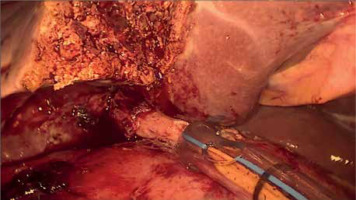

PM should be prepared before parenchymal transection for possible immediate application. It can be performed intracorporeally and extracorporeally. For an intracorporeal PM a long cotton tape is placed around the hepatoduodenal ligament through a 12 mm trocar, then passed through a small tourniquet and clipped 2–3 cm above it. For occluding the hepatic inflow, the tourniquet is pushed toward the hepatic pedicle and clipped above it. Pedicle clamping may also be performed with a laparoscopic bulldog clamp or appropriately prepared Foley’s catheter (Photo 3) [22]. For an extracorporeal PM the tape is externalized through a trocar and passed through the catheter placed above the trocar. The main advantage of the extracorporeal technique is the possibility for clamping by the assistant surgeon, without distraction of the main surgeon (Photo 4). When comparing both techniques of PM in retrospective studies, extracorporeal PM carries more practical advantages, but it still requires further research [23]. PM can be continuous or intermittent (most commonly 15 : 5 min ratio or 10 : 5 min ratio in cirrhotic liver). In HCC patients, according to a recent RCT, 25 min intermittent PM results in lower BL, as well as higher transection speed [24]. However, the performed PM technique depends on surgeons’ preferences and estimated operative time.